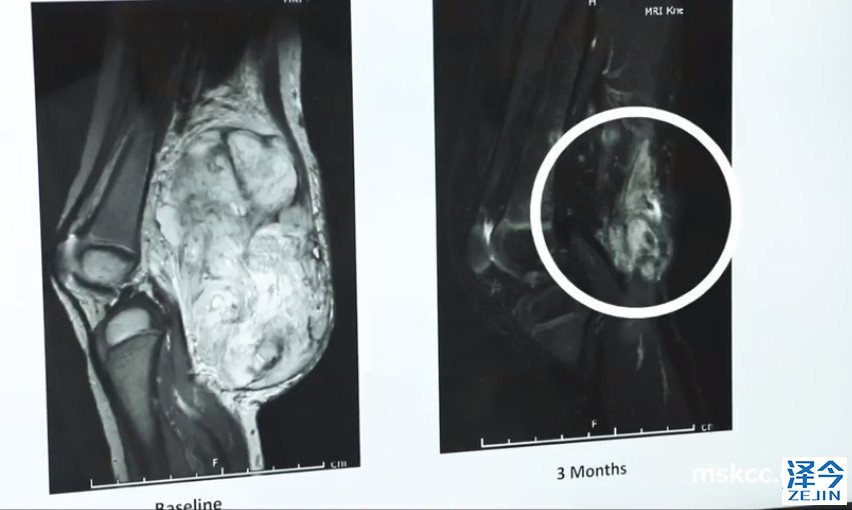

虽然她在服药几个月后,影像学检查发现复发很少,她持续服用药物。如今,安娜的扫描显示:没有活性的证据,也就是说癌症病灶没有活性,不会再有复发转移的机会,癌症没有了!